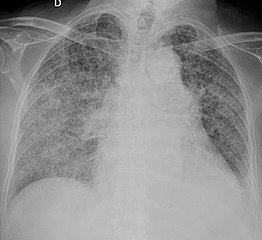

| Chest X ray showing miliary tuberculosis | |

X-ray, showing bilateral interstitial infiltrates

X-ray, showing extensive bilateral reticulo-nodular infiltrates